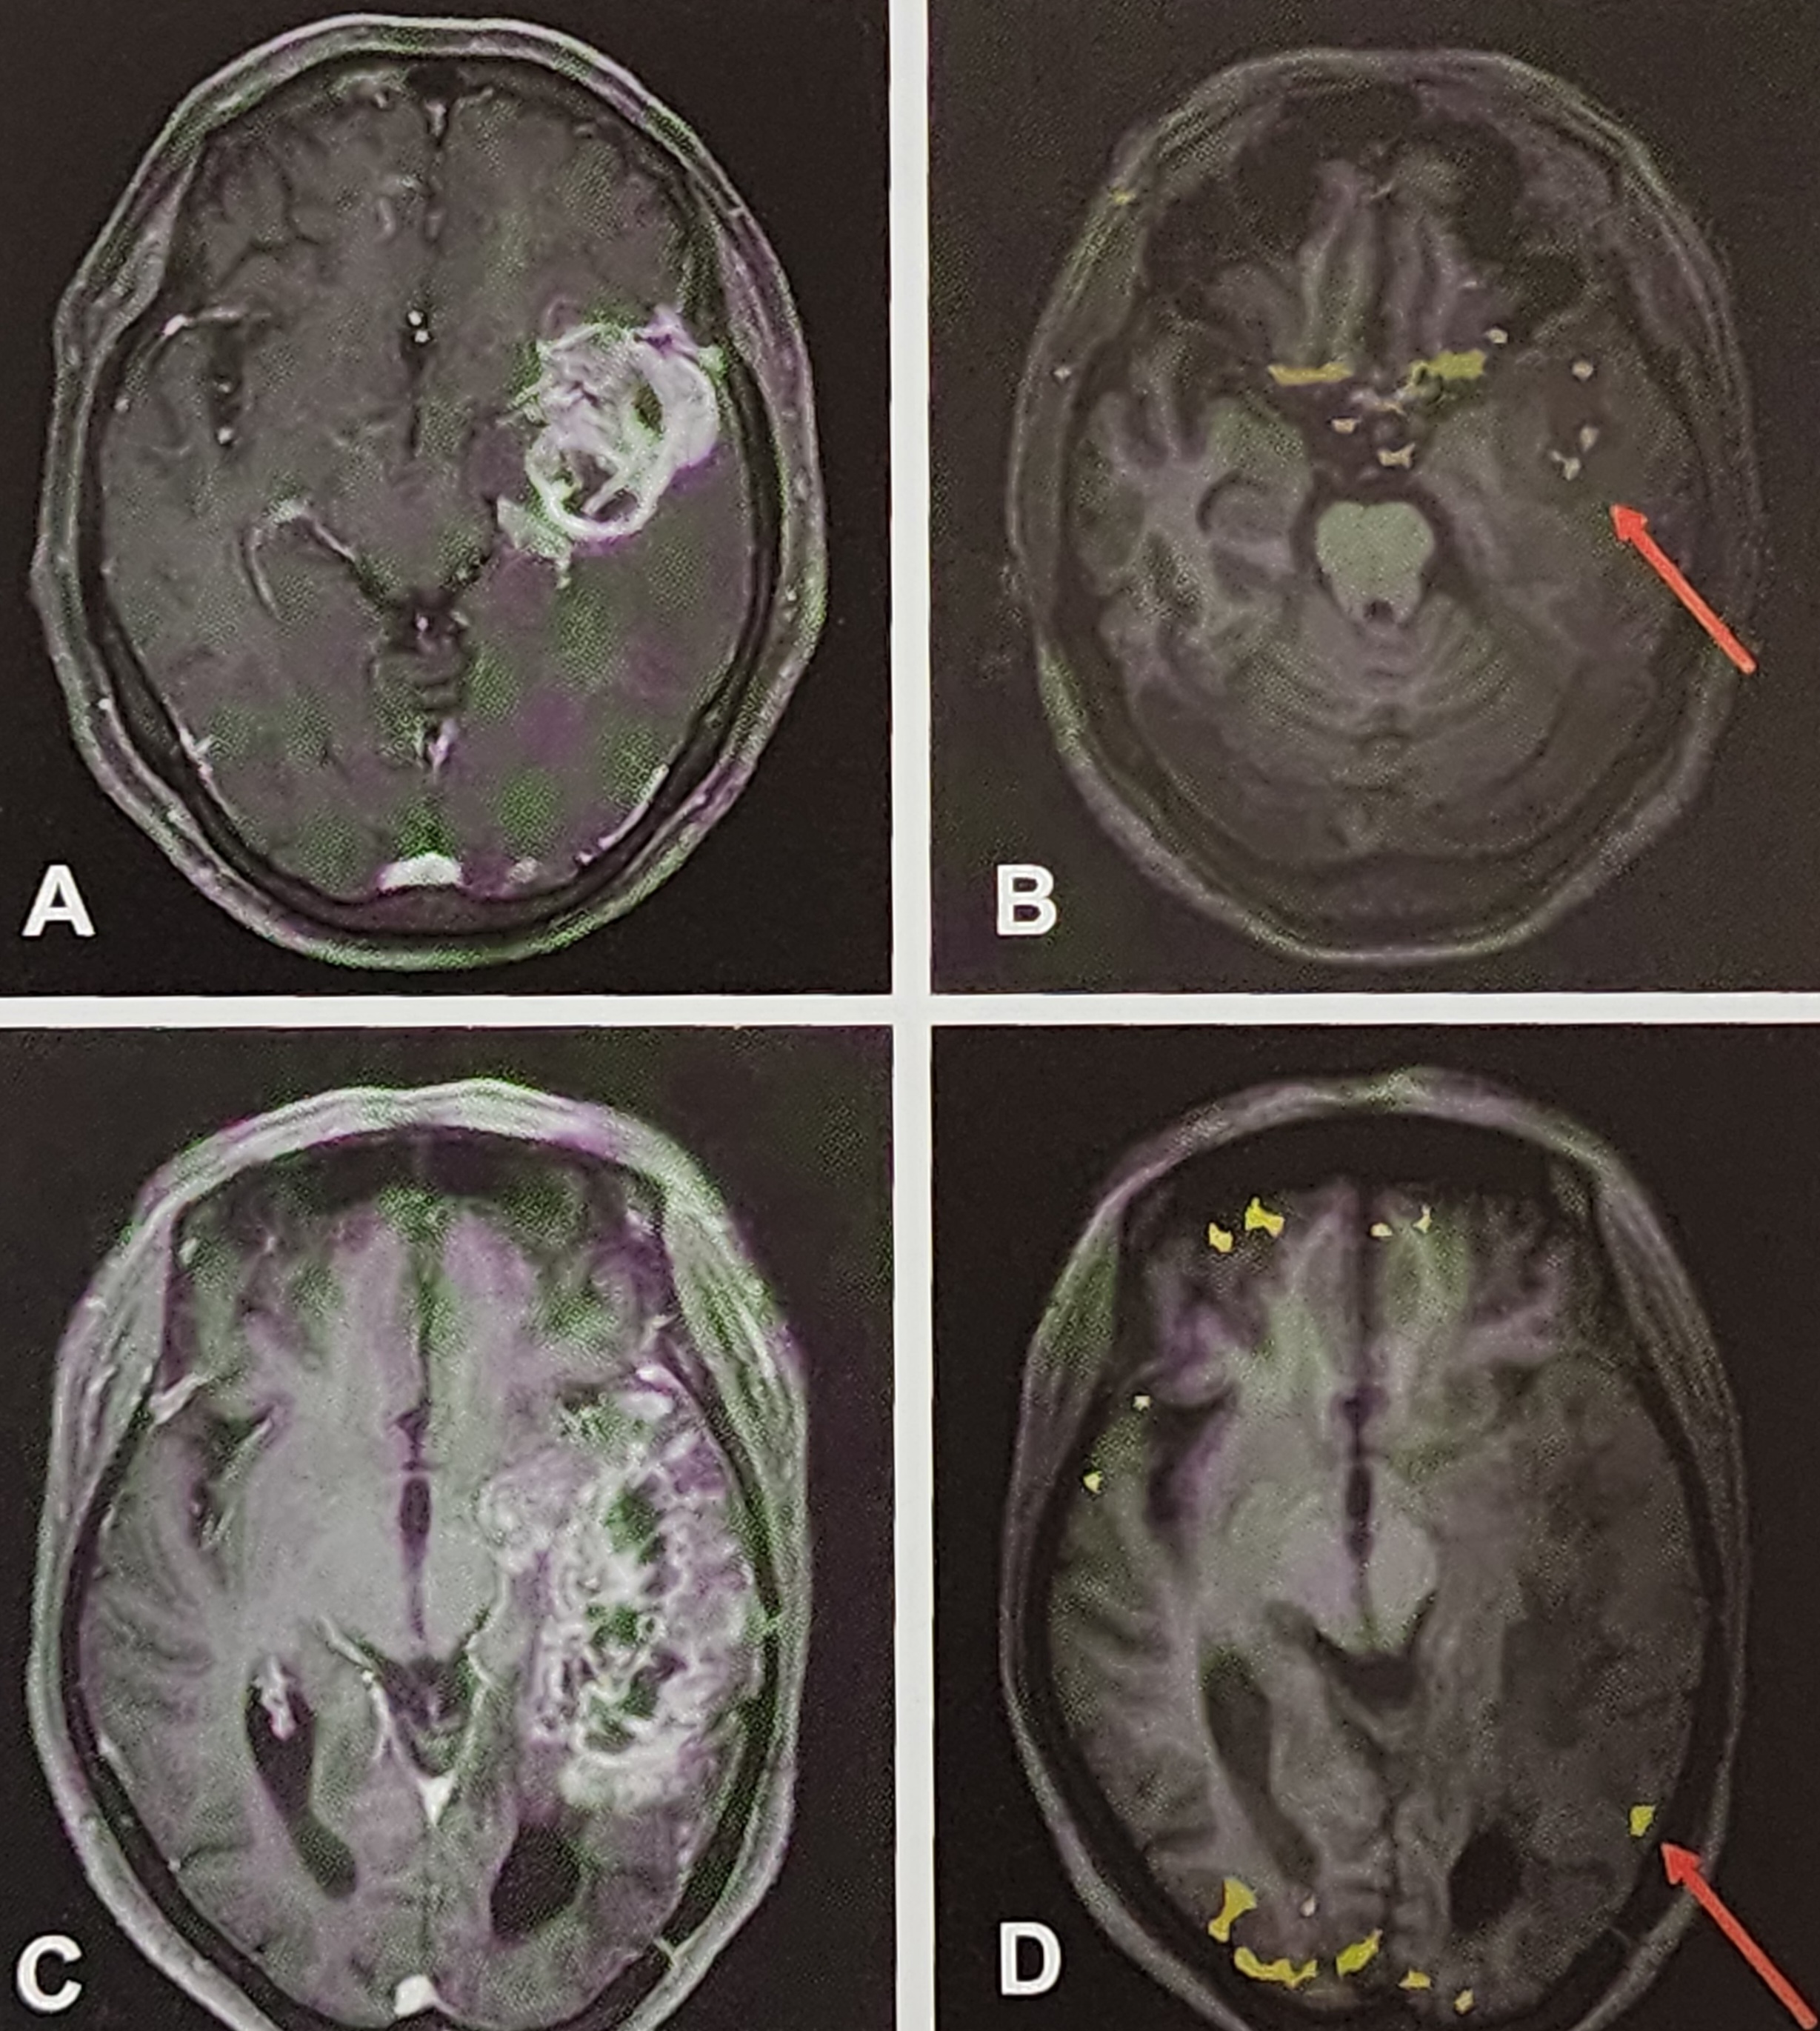

FDG-PET는 방사성 동위원소를 이용하여 뇌의 대사 상태를 분석하는 기술입니다. 이 기술은 특히 포도당 대사가 활발한 영역과 비활성화된 영역을 명확히 보여줄 수 있어 뇌전증, 치매, 뇌종양과 같은 신경 질환을 진단하는 데 널리 사용됩니다.

FDG-PET 사례

예를 들어, 내측두엽뇌전증(Medial Temporal Lobe Epilepsy)에서는 MRI로 명확히 보이지 않는 해마의 대사 저하를 FDG-PET로 확인할 수 있습니다. 이는 특히 약물 난치성 뇌전증 환자의 수술 성공률을 높이는 데 기여합니다.

3. SPECT(단일광자 방출 단층촬영)의 원리와 응용

SPECT는 FDG-PET와 유사하게 방사성 동위원소를 활용하지만, 혈류 변화를 측정하는 데 초점을 맞춥니다.

- 발작기 SPECT는 발작 부위의 국소 혈류 증가를 보여줍니다.

- 간격기 SPECT는 발작 부위의 혈류 저하를 시각화.

SPECT의 한계와 FDG-PET과의 차이점

- SPECT는 FDG-PET에 비해 공간 해상도가 낮아 미세 병변 분석에 한계가 있습니다.

- 그러나 혈류 변화와 대사 변화가 동시에 필요한 경우 SPECT는 FDG-PET을 보완하는 역할을 할 수 있습니다.

- FDG-PET과 SPECT

- FDG-PET은 대사 변화를, SPECT는 혈류 변화를 측정합니다.

- 두 기술을 통합하면 발작 부위를 더 정밀하게 분석할 수 있습니다.